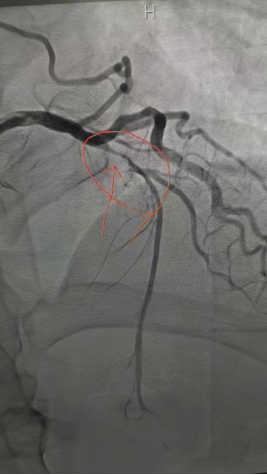

造影显示该患者为近端次全闭塞——几乎堵死了。手术团队精准操作,植入1枚药物球囊后,该患者症状立即缓解。